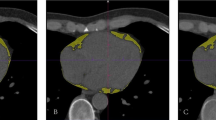

Segmentation of the left ventricle

The overall acquisition, processing, and analysis framework of the datasets. Both EID-CT and PCD-CT datasets of enrolled patients were segmented (a) by two readers. A total of 18 first-order, 75 textural, and 17 shape-based radiomic features were extracted (b) from the segmented volume of interests. These values were then compared (c) between EID-CT and PCD-CT reconstructions, among different VMIs, and between different segmentations to assess inter-reader agreement. EID-CT, Energy-integrating detector CT; GLCM, Gray level co-occurrence matrix; GLDM, Gray level dependency matrix; GLRLM, Gray level run length matrix; GLSZM, Gray level size zone matrix; NGTDM, Neighboring gray-tone difference matrix; PCD-CT, Photon-counting detector CT; VMI, Virtual monoenergetic image